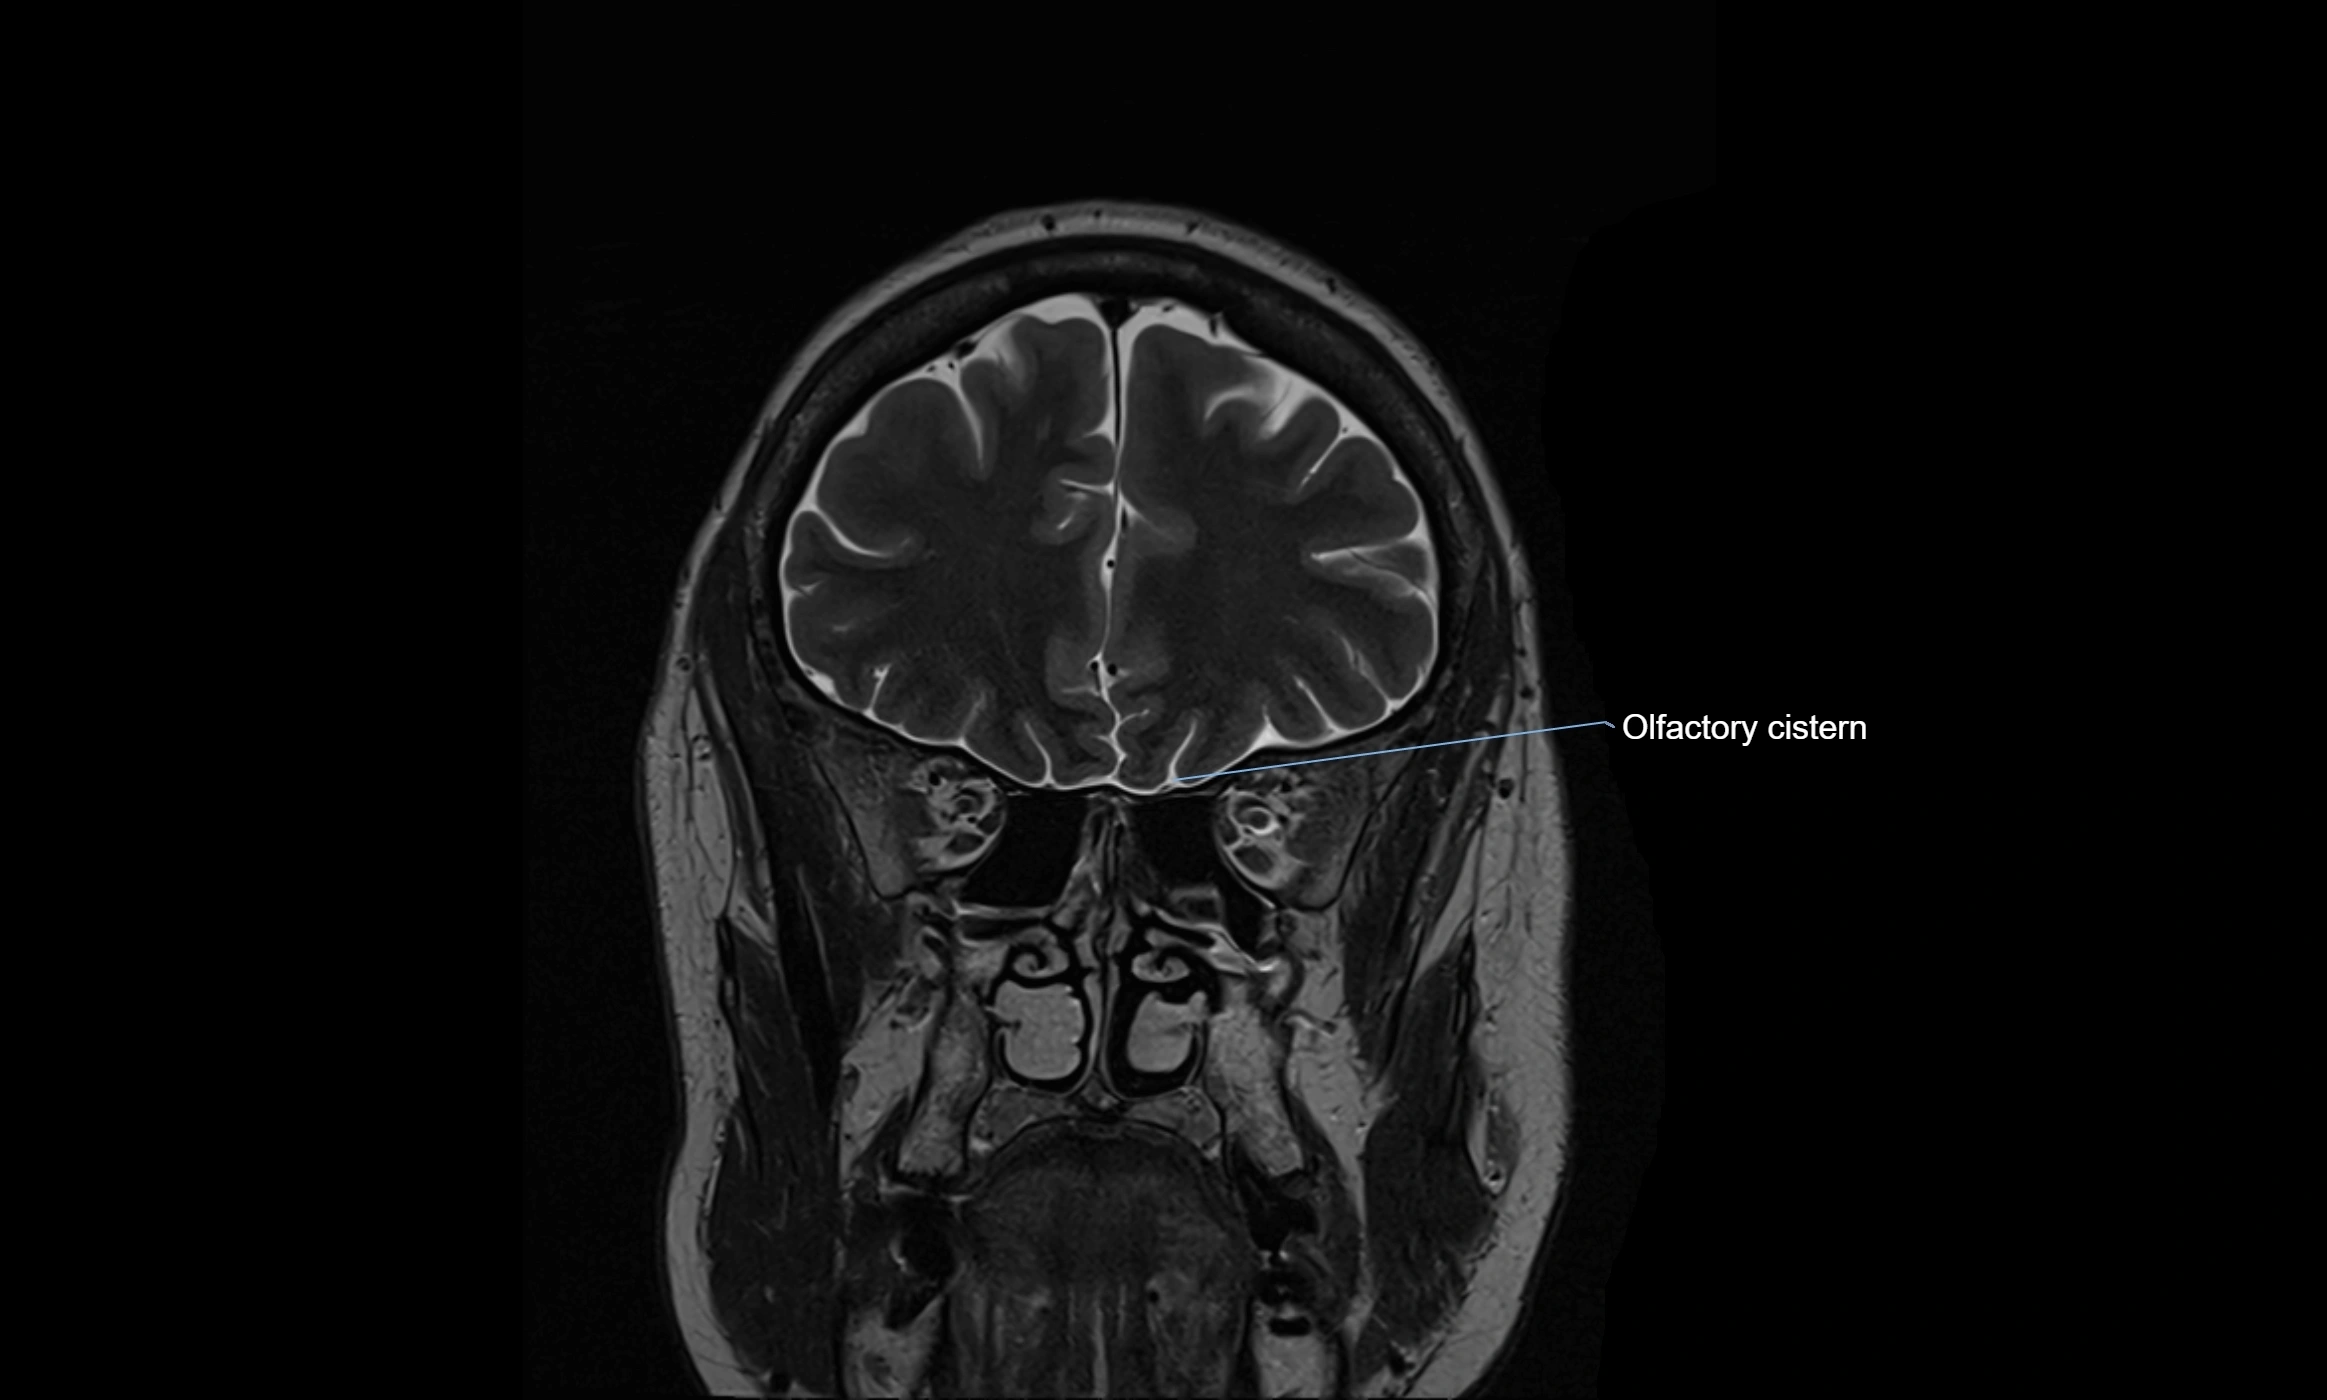

MRI images

image